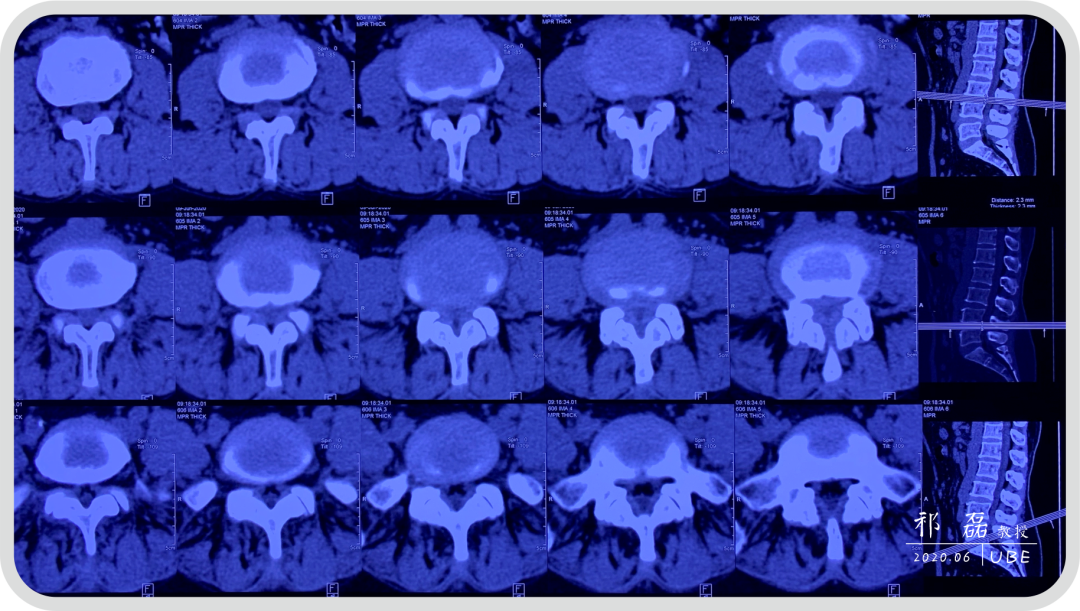

患者:吴某,女,53岁,腰痛及双下肢疼痛麻木5年余,加重1月余,间歇性跛行约200米。于近日入我院查体,下腰椎棘突及椎旁肌深压痛,双下肢感觉运动正常。双侧直腿抬高试验(-),双侧踝反射(-),入院诊断为:腰椎管狭窄症。

图2:腰椎CT